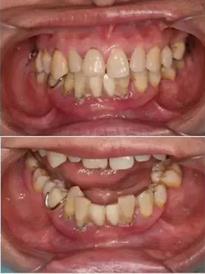

初診時(shí)下前牙不良修復(fù)體

去除不良修復(fù)體后鄰牙松動(dòng)